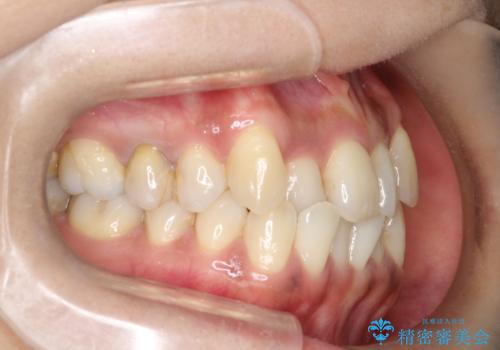

【審美装置】抜歯の本数最小限で行った矯正治療

- 治療計画

- 全体のがたつきを主訴に来院されました。4番目の歯を4本抜歯も検討しましたが、口元が下がりすぎてしまうリスクと2番目の転位うが著しく並べるのにかかる期間を考慮し、変則的な抜歯をし、並べる計画を立てました。

抜歯矯正のため2年はかかってしまいましたが、きれいに並び患者様にも満足頂きました。